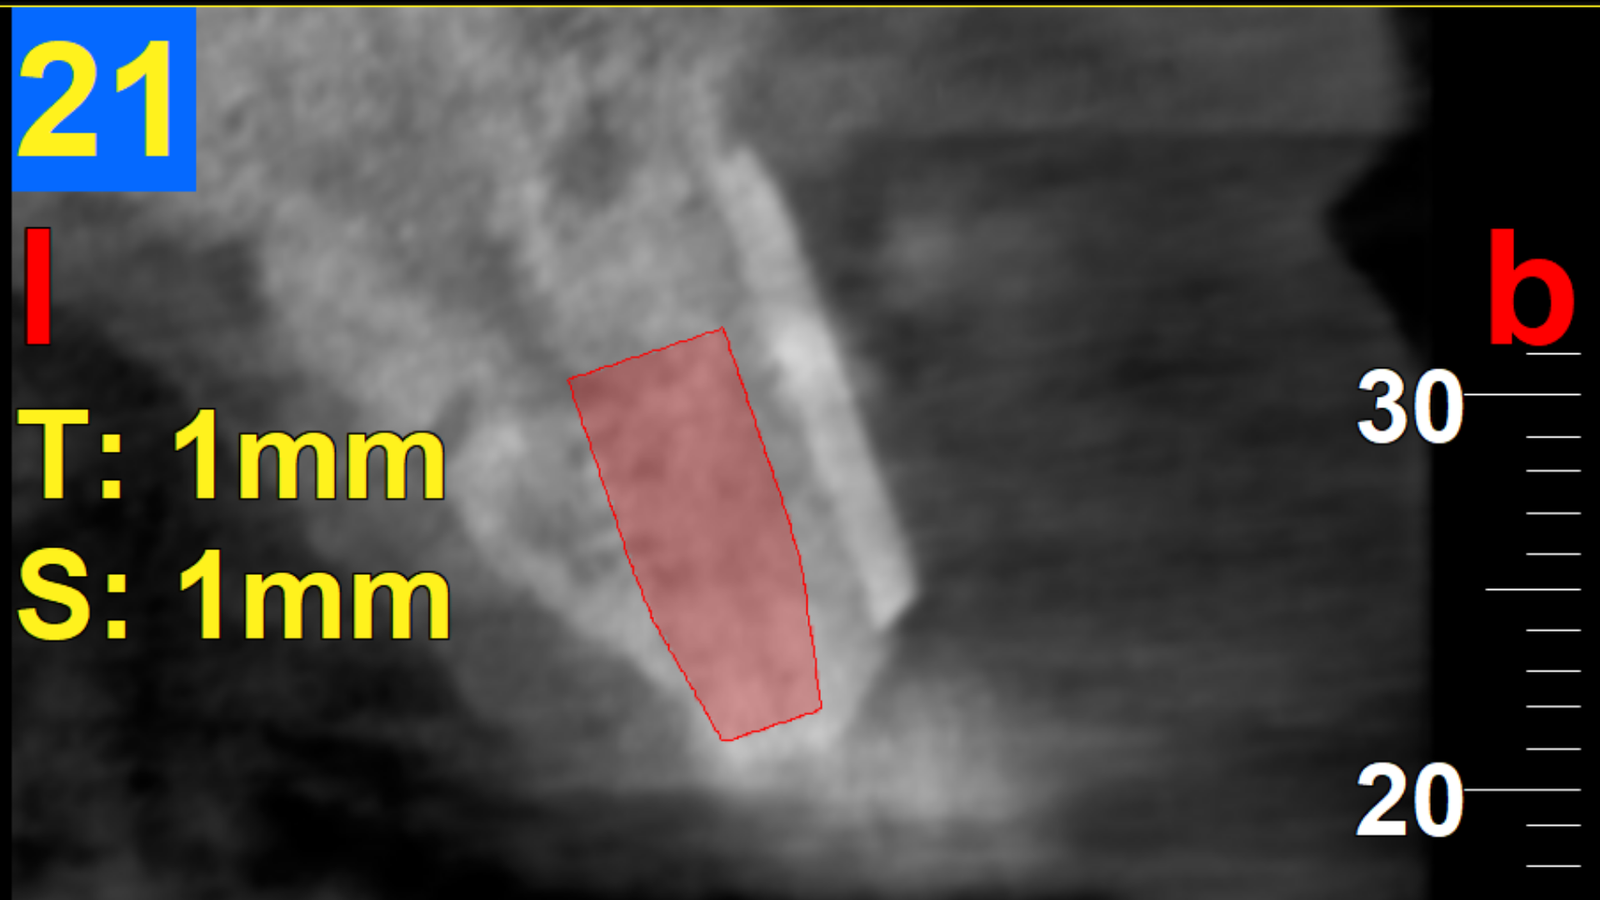

Un patient se présente avec une incisive centrale droite (11) dévitalisée, ainsi que l’incisive latérale homolatérale (12), également dévitalisée.

Ces deux dents présentent des images de résorption osseuse discrète en rapport avec la dévitalisation, avec un kyste de 12 mm au niveau de la 12.

11 : extraction avec greffe osseuse (mélange os bovin + os du patient prélevé au niveau du ramus), le tout recouvert d’une membrane et fixé avec des pins.

12 : résection de la partie apicale avec un remplissage rétrograde au MTA.

À 6 mois : mise en place d’un implant.

3 mois après : mise en place d’une couronne vissée en zircone.